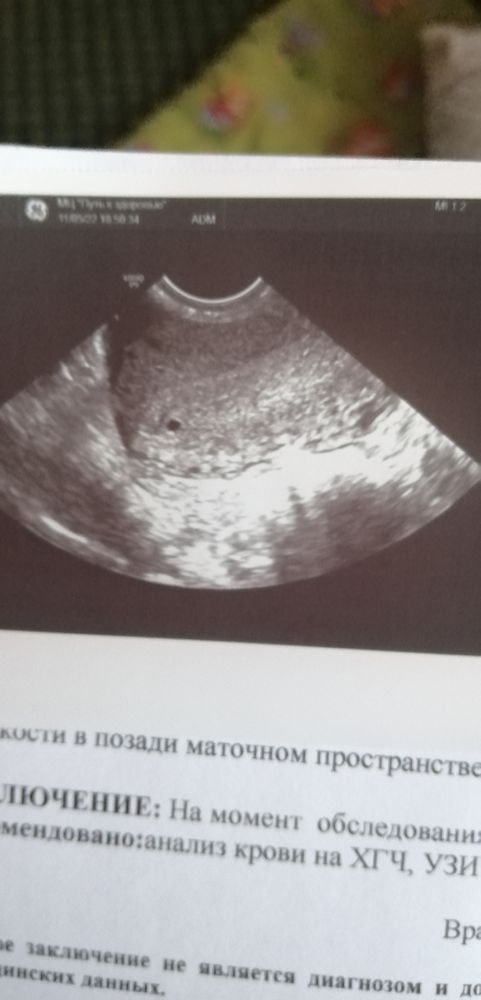

Пока здесь вижу хорошее красивое плодное яйцо малого срока-контур ровный, ободок четкий. Не совсем понятно почему и с чего ЗБ, если это только первое узи, которое показало плодное яйцо в матке и нет данных по ХГЧ.

А какой у Вас хгч? Вижу точку на узи - начало зарождения новой жизни)) Чего сразу зб то...